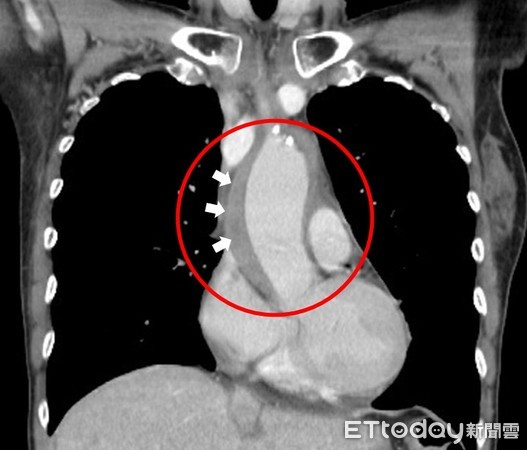

一名55岁女性突感撕裂性胸痛,确诊升主动脉壁内血肿。(图/医院提供,下同)

一名55岁王女士突然连续三天都感到「撕裂性胸痛」,就医检查发现收缩压高达210毫米汞柱,从胸部电脑断层扫描看到升主动脉被一圈血块包围,确诊「升主动脉壁内血肿」,接下来恐发生剥离,立刻紧急手术。医师提醒,撕裂般胸痛、有血压飙高、胸闷、冒冷汗、下肢无力、晕眩和昏迷都是急性主动脉症候群的表现,一定要特别留意。

收治该病例的台北慈济医院心脏血管外科徐展阳医师指出,急性主动脉症候群患者若未即时治疗,有50%的病患在48小时内死亡,91%会在6个月内死亡,而从王女士胸部电脑断层扫描看到升主动脉被一圈血块包围,最厚处约有1.5公分,经药物积极降压后,血肿仍未改善,紧急进行升主动脉置换手术,才康复出院,并定期门诊追踪。